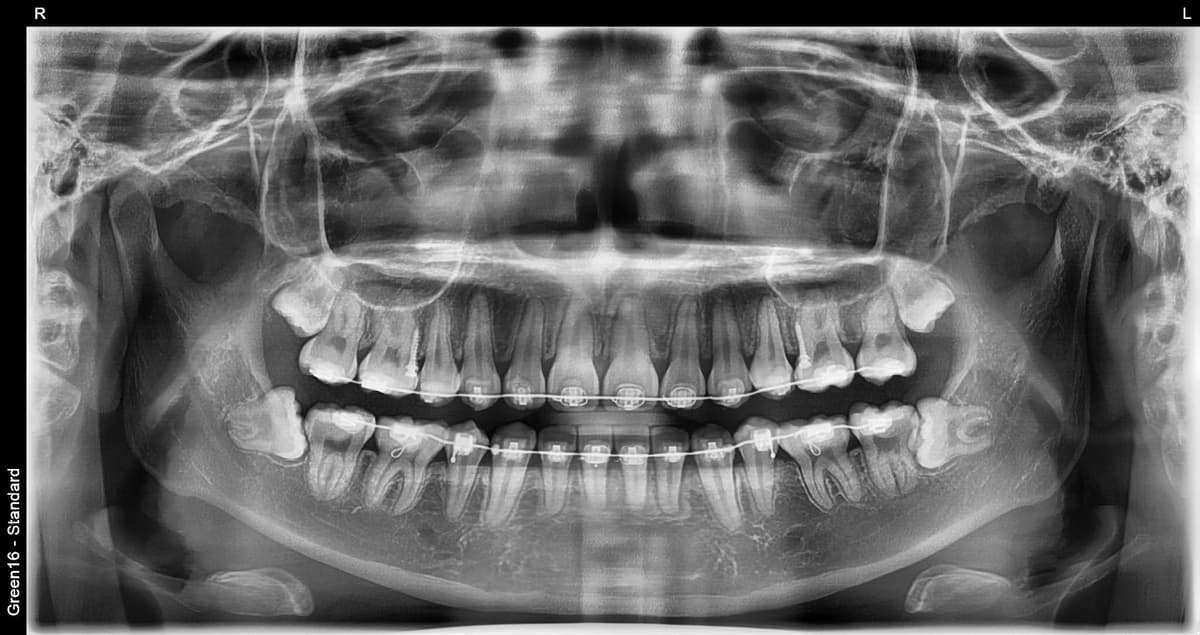

RISK LEVELS

Aql tishi holatiga qarab xavf darajasi

After

O'rta xavf

Qisman ko'milgan aql tishi

Ovqat qoldiqlari yig'ilib qolishi oson va yallig'lanish tez-tez yuzaga keladi

Yuqori xavf

To'liq ko'milgan aql tishi

Kista hosil bo'lishi mumkin bo'lgani uchun erta sug'urib olish kerak

Ortodontiya davrida aql tishi

Ortodontiya davolash jarayonida aql tishini sug'urib olish zarur bo'lgan holat

Murakkab ko'milgan aql tishi - milkda chuqur yashiringan bo'lsa ham OK

Asabga yaqin aql tishi - asab shikastlanishi xavotiri yo'q xavfsiz olish

Gorizontal ko'milgan aql tishi - yonga yotgan murakkab hollarni ham bajara olamiz